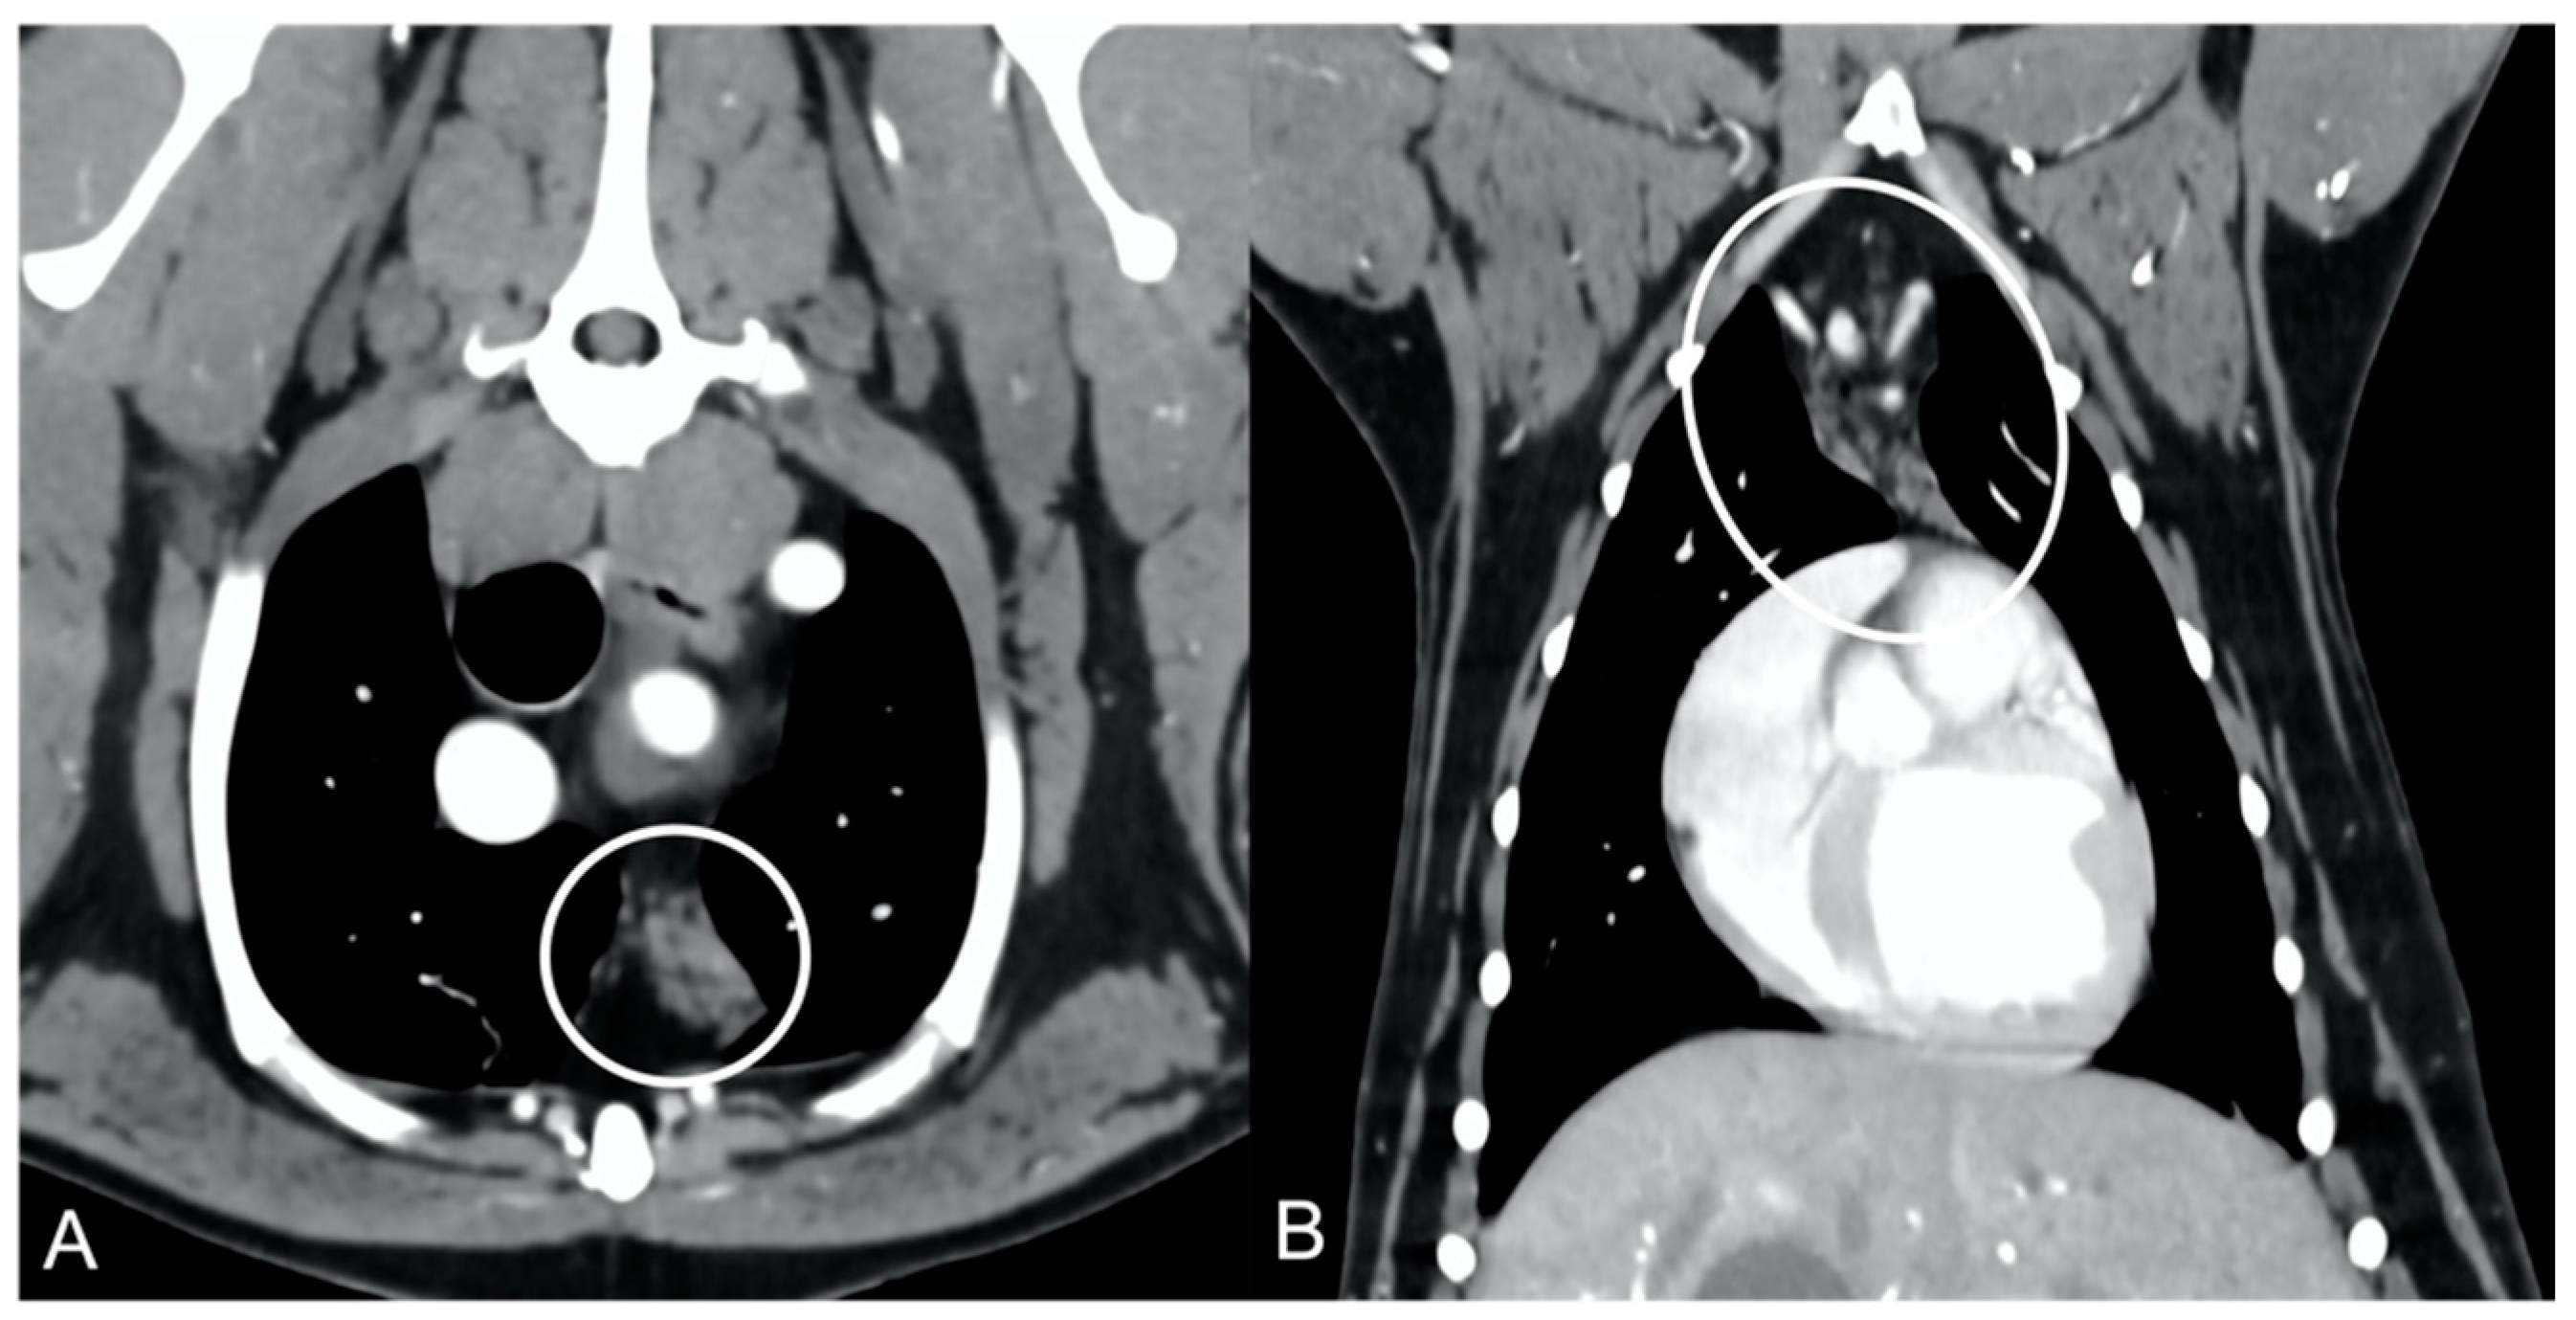

The overall appearance was lobulated in all of the adult dogs and homogeneous in all of the juvenile dogs (Figure 1 and Figure 3). The thymus was left-sided in all of the adult dogs, while it was located in the midline in a few juvenile dogs; one presented a thymus on the right side due to situs inversus (Figure 4). The maximum dimension of the thymus in the adult dogs group was always the length, while in some juvenile dogs, the maximum diameter was the width (Figure 2). The dimensions of the thymus were variable between different patients, with several breeds included and large differences in body weight between the dogs. For this reason, a ratio between the maximum diameter of the thymus (measured in cm) and the body weight (measured in kg) was calculated for each dog. The median ratio in the adult dogs group was 0.2 (minimum: 0.06; maximum: 0.4), while in juvenile dogs, it was 0.4 (minimum: 0.1; maximum: 1.4). The dogs with the higher ratio (>1) were in the juvenile group and they presented with spinal a cyst and enteritis and were 6 and 7 months old, respectively. The dogs with the lower ratio (<0.1) were in the adult group and they presented with muscular hemangiosarcoma (one dog) and synovial cell sarcoma (two dogs) and were 2, 6, and 8 years old, respectively.

The thymus was less attenuating in adult dogs compared to young dogs, with a median of the mean pre- and post-contrast attenuation values lower in adult dogs compared to juvenile dogs (Table 1). In 5/11 (45%) adult dogs, the minimum pre-contrast attenuation values were negative values (from −22 to −2 HU), due to the presence of multiple, hypoattenuating, thick septi within the thymic parenchyma (Figure 5).

Figure 3. Appearance of the parenchyma of the thymus (circled) in an adult dog (A) compared to a young dog (B). Post-contrast transverse CT images. The appearance is lobulated in adult dogs (A) and homogeneous in young dogs (B).